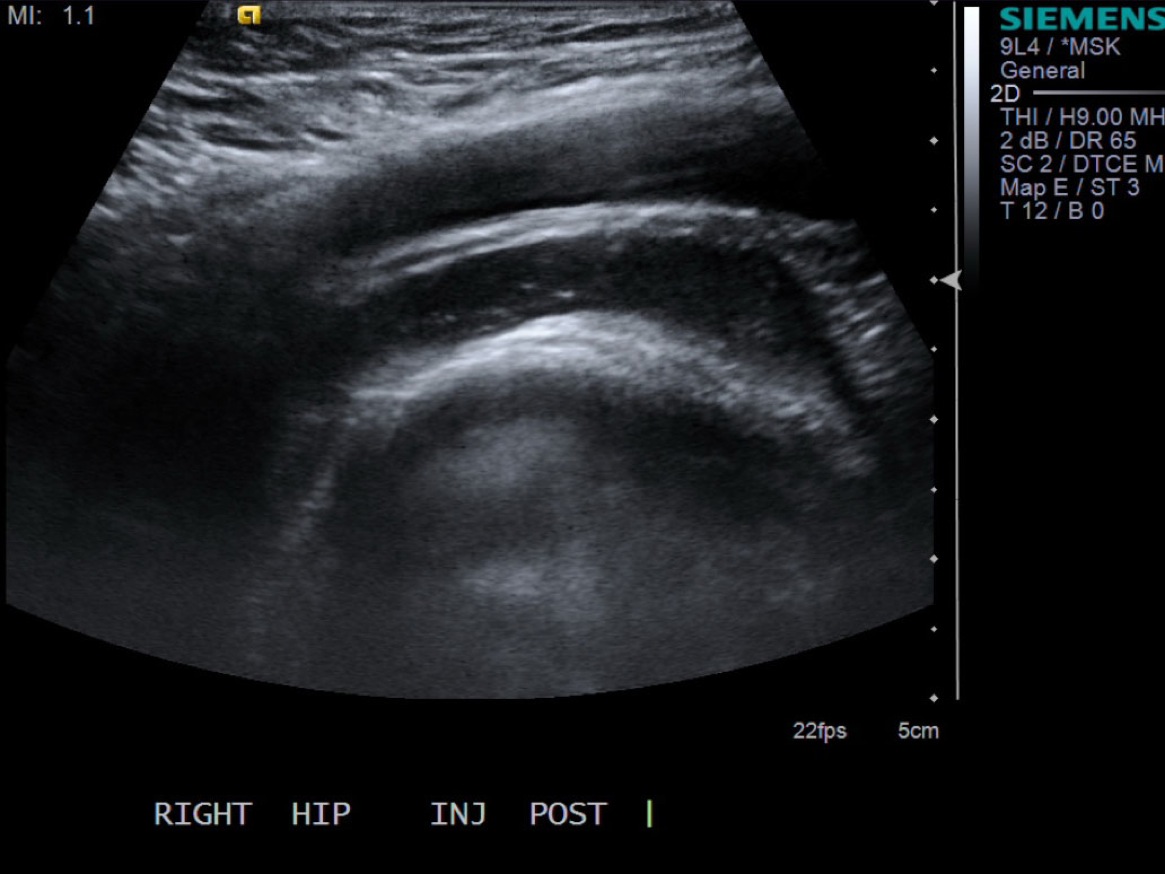

12. Scan joint to demonstrate distention. Can try to flex hip to see if fluid distended.

• descriptiondescription